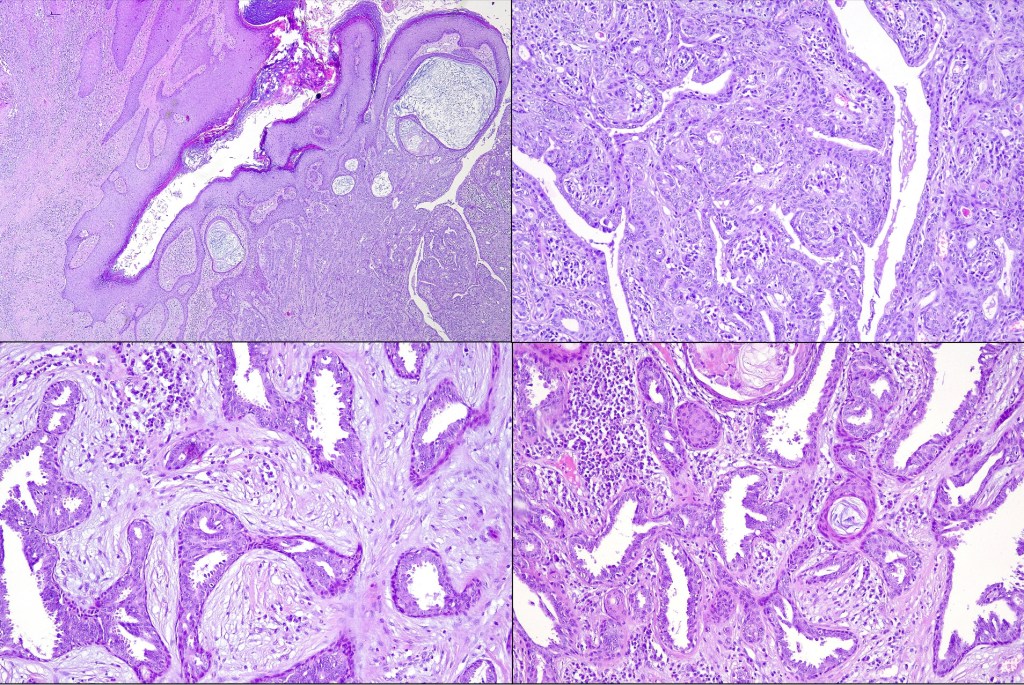

Histological features

•Hamartoma characterized by abnormalities of epidermis, hair follicles, sebaceous glands, apocrine sweat glands & connective tissue

•Epidermis often papillomatous

•Follicular induction is common & sometimes trichoblastomatous foci are evident

•High, increased hyperplastic, sebaceous glands with openings onto the surface epithelium (in. old lesions, they may be absent)

•Reduced hair follicles

•Excessive numbers of apocrine glands

•May be complicated by a wide range of tumors (which are often multiple) including trichilemmoma, trichoblastoma, SCAP, sebaceous tumors, sweat gland tumors, melanocytic nevi & rarely by malignant tumors including BCC, SCC, melanoma, trichilemmal carcinoma, apocrine carcinoma & microcystic adnexal carcinoma